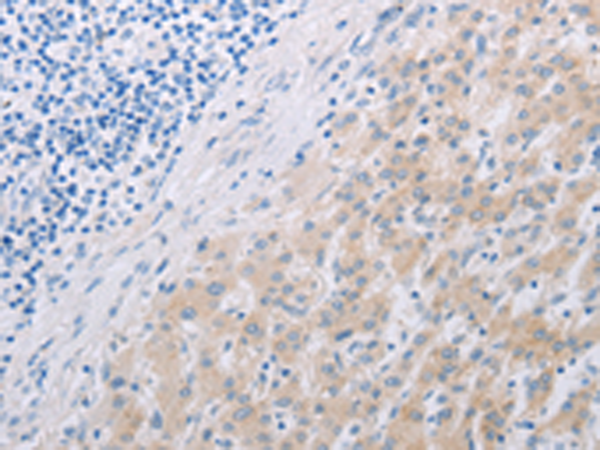

分类: 科研抗体货号: P04084别名: CD11A, LFA-1, LFA1A应用: IHC反应种属: Human